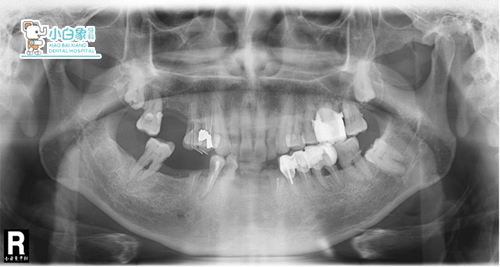

口内查:16缺失,14,15见白色充填材料,18低位未萌出。

26间一钢冠修复体,28低位未萌出。

34,35,36见修复体,

37近中邻面龋坏,牙根暴露1/3,松动2度,

温度试验敏感,牙龈无红肿。

38低位未萌出。

44合面见白色充填物,45残根,46缺失,

48未见。

诊断:上颌牙列缺损

37慢性牙髓炎

下颌牙列缺损